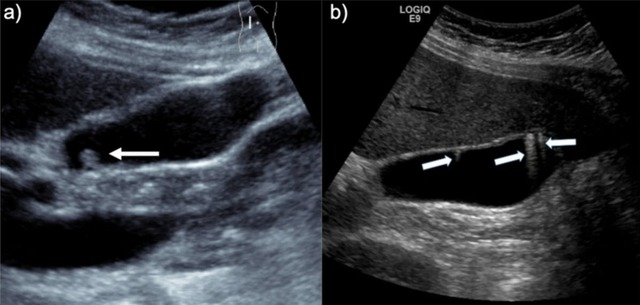

Sỏi mật là bệnh lý phổ biến tại gan mật, có thể âm thầm tồn tại nhiều năm nhưng cũng có lúc gây đau dữ dội, nhiễm trùng, thậm chí nguy hiểm tính mạng. Nhờ sự phát triển của y học hiện đại, việc chẩn đoán và điều trị sỏi mật ngày càng chính xác, hiệu quả và ít xâm lấn hơn.

Trong nhiều trường hợp, sỏi mật được phát hiện tình cờ qua siêu âm định kỳ hoặc khi kiểm tra các vấn đề khác. Nếu người bệnh không có triệu chứng (như đau, sốt, rối loạn tiêu hóa), phần lớn bác sĩ khuyên nên chỉ theo dõi định kỳ, kết hợp chế độ ăn uống lành mạnh và duy trì cân nặng hợp lý.

Khi sỏi rơi vào ống mật chủ, gây tắc nghẽn và viêm đường mật, bác sĩ sẽ tiến hành nội soi mật tụy ngược dòng (ERCP) để lấy sỏi qua đường miệng mà không cần mổ. Đây là thủ thuật phổ biến tại các bệnh viện lớn, hiệu quả cao và ít xâm lấn, giúp giảm biến chứng cấp tính.